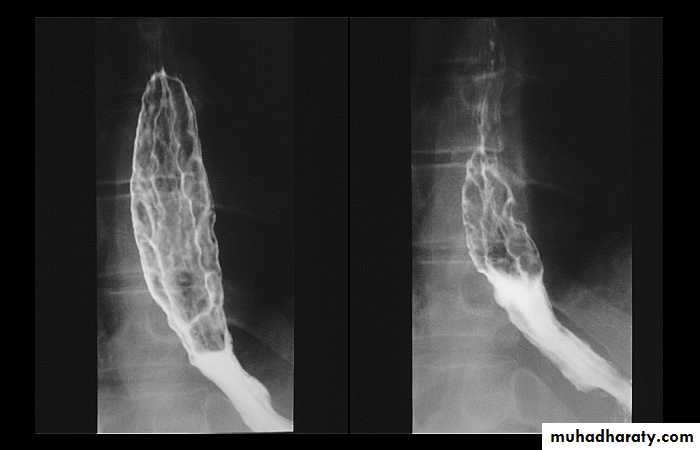

Infectious esophagitis

Candida esophagitis in patient with an infectious esophagitis due to candida , the barium shows numerous fine erosions & plaques causing shaggy outline of the osophagus due to Candida albicans in immunocompromised patient.middle year old female with a past medical history significant for HIV/AIDS comes in with complaint of loosing their weight over the past 2 weeks with pain & difficulty on swallowing …. Also feels like food is getting stuck in her throat